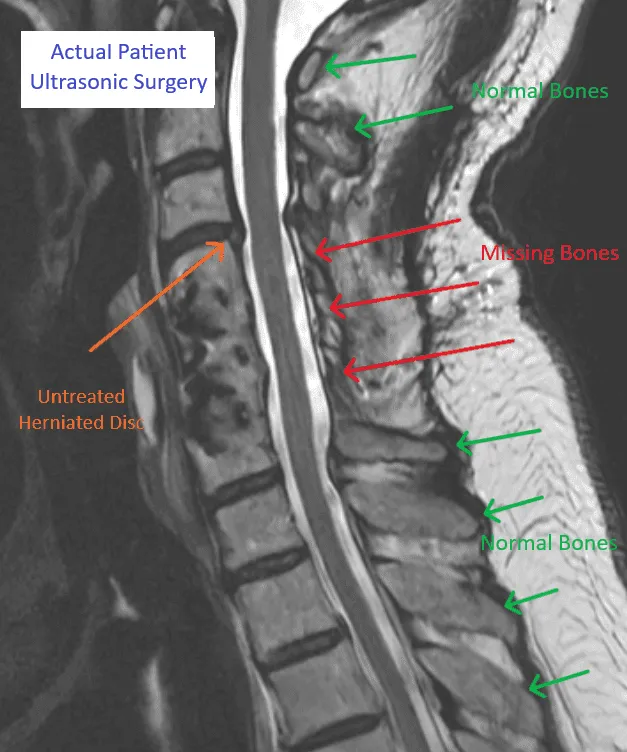

MRI image of a spine showing areas with normal and missing bones labeled in green and red.

Destruction of Stabilizing Bones

Medical scan showing normal and missing spinal bones with herniated disc, labeled for ultrasonic surgery.

Pain Source NOT Treated